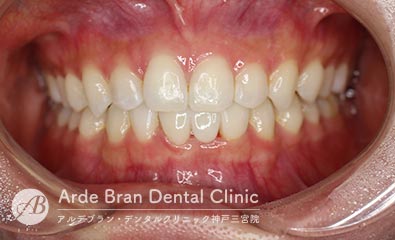

- 叢生/過蓋咬合/シザースバイト(20代女性 治療期間1年5カ月)

- 歯のがたつきと突出感を改善したいとの事でご来院されました。当院で精査した所、奥歯の前後的な位置関係にもズレがあり、前歯のかみ合わせも深く、また左側の奥歯も一部かみ合っていない場所がありました。顎間ゴムを用いて奥歯の前後的な位置関係を改善し、かみ合わせも整えました。なるべく目立たない装置で、可能であれば歯を抜きたくないとの事だったのでインビザラインフルにて治療を行いました。

- 治療前

- 治療後

| 装置名 | インビザライン(マウスピース矯正) |

| 抜歯非抜歯 | 非抜歯 |

| 治療期間 | 1年5カ月 |

| 費用 | インビザラインフル72万円+TAX 再印象(5千円+TAX)×1回 顎間ゴム500円×数個 |

| リスク副作用 | 装置装着による違和感、歯の移動時の痛み、歯根吸収など。詳しくはこちらをご参照ください。 |